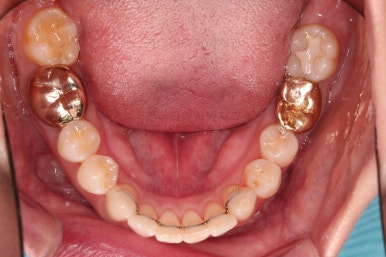

마찬가지로 부산치아교정비용 초진 시 입안의 모습입니다.

아랫니가 많이 보이지 않는 타입이라서 잘 몰랐는데 입안을 관찰해 보니 아래 앞니가 삐뚤어 있네요.

이 부분도 꼭 교정해야 될 정도는 아니여서 선택의 문제라고 할 수 있는데요.

어금니가 문제였습니다.

윗니 어금니가 하나 없는 상태였고요.

어금니가 없이 지낸지 꽤 시간이 흐른터라 뒤쪽 어금니가 앞으로 쓰러져 공간을 잠식하고 있었습니다.